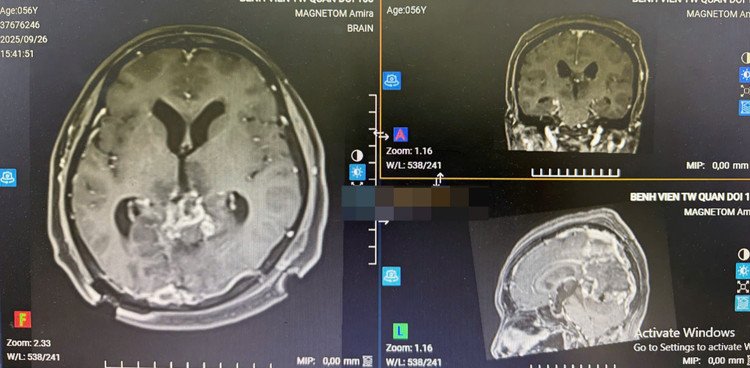

Phim chụp CT trước phẫu thuật - Ảnh BVCC

Phim chụp CT sau mổ - Ảnh BVCC